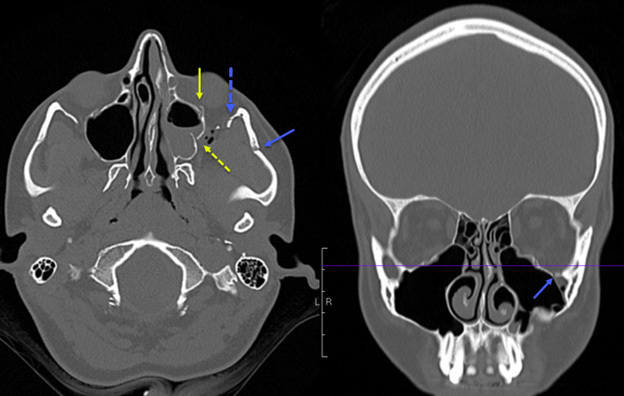

Figure 1 shows a slice of a CT scan in both the axial and coronal planes that provides an example of a ZMC fracture in a pediatric patient. The image demonstrates an anterior and posterior maxillary sinus wall fractures, zygomatic arch fracture, inferior orbital rim fracture, and lateral orbital rim fracture.

Figure 1. Computed Tomography Scan of Zygomaxillary Complex Fracture |

The image demonstrates an anterior and posterior maxillary sinus wall fractures, zygomatic arch fracture, inferior orbital rim fracture, and lateral orbital rim fracture. Image courtesy of Mantosh S. Rattan, MD, Radiologist, Orlando Health Arnold Palmer Children’s Hospital, Orlando, FL. |